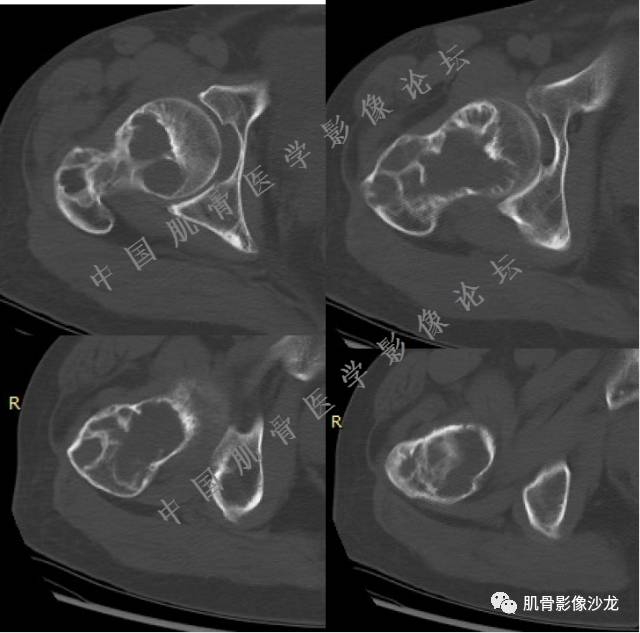

主诉:右大腿疼痛、活动受限20天

现病史:患者于20天前无明显诱因出现右下肢疼痛,活动受限,疼痛呈阵发性,活动后加重。自行口服止痛药芬必得,效果不佳,至当地医院治疗,检查发现右侧股骨近端病变。遂来诊

葛英霖 20:30 原发或继发动脉瘤样骨囊肿,继发于巨细胞瘤,软骨母,纤维组织细胞瘤,骨母等等

向以四 20:30 软骨母合并ABC,

医影在线 20:30 软骨母,/继发ABC

飞鹰行动 20:31 T2信号高,有软骨成分

Echo 20:32 T2确实有一块区域很亮 ,并有野液平

飞鹰行动 20:33 有侵袭性

飞鹰行动 20:35 骨皮质破坏,周围骨质异常信号

葛英霖 20:36 这不是良性病变

葛英霖 20:36 中间型可能性极大

葛英霖 20:37 明显侵蚀骨内膜啊,硬化边也不完整 (细箭头所示)

葛英霖 20:43 提不提也很明显继发了abc

葛英霖 20:44 是

葛英霖 20:46 明显的多囊状改变,液液平面